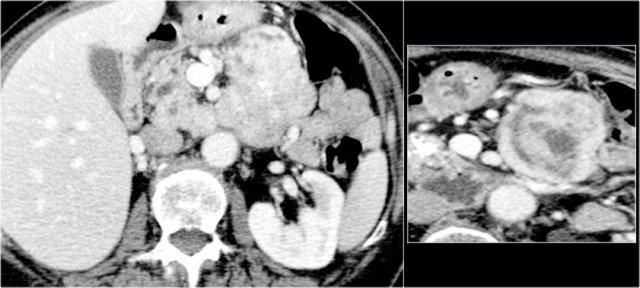

Hình CT bên trái là của một bệnh nhân có tiền sử viêm tụy.

Có hai nang đơn ngăn hay nang đơn giản.

Lưu ý thêm hình ảnh thâm nhiễm mỡ sau phúc mạc bên phải.

Chẩn đoán có khả năng nhất là nang giả.

Hình CT bên phải cho thấy một nang ở đuôi tụy ở một phụ nữ 36 tuổi, được phát hiện tình cờ qua siêu âm.

Nang có bờ dày không đều và chứa các thành phần đặc ‘không phụ thuộc trọng lực’.

Chẩn đoán có khả năng nhất là u nang tân sinh.